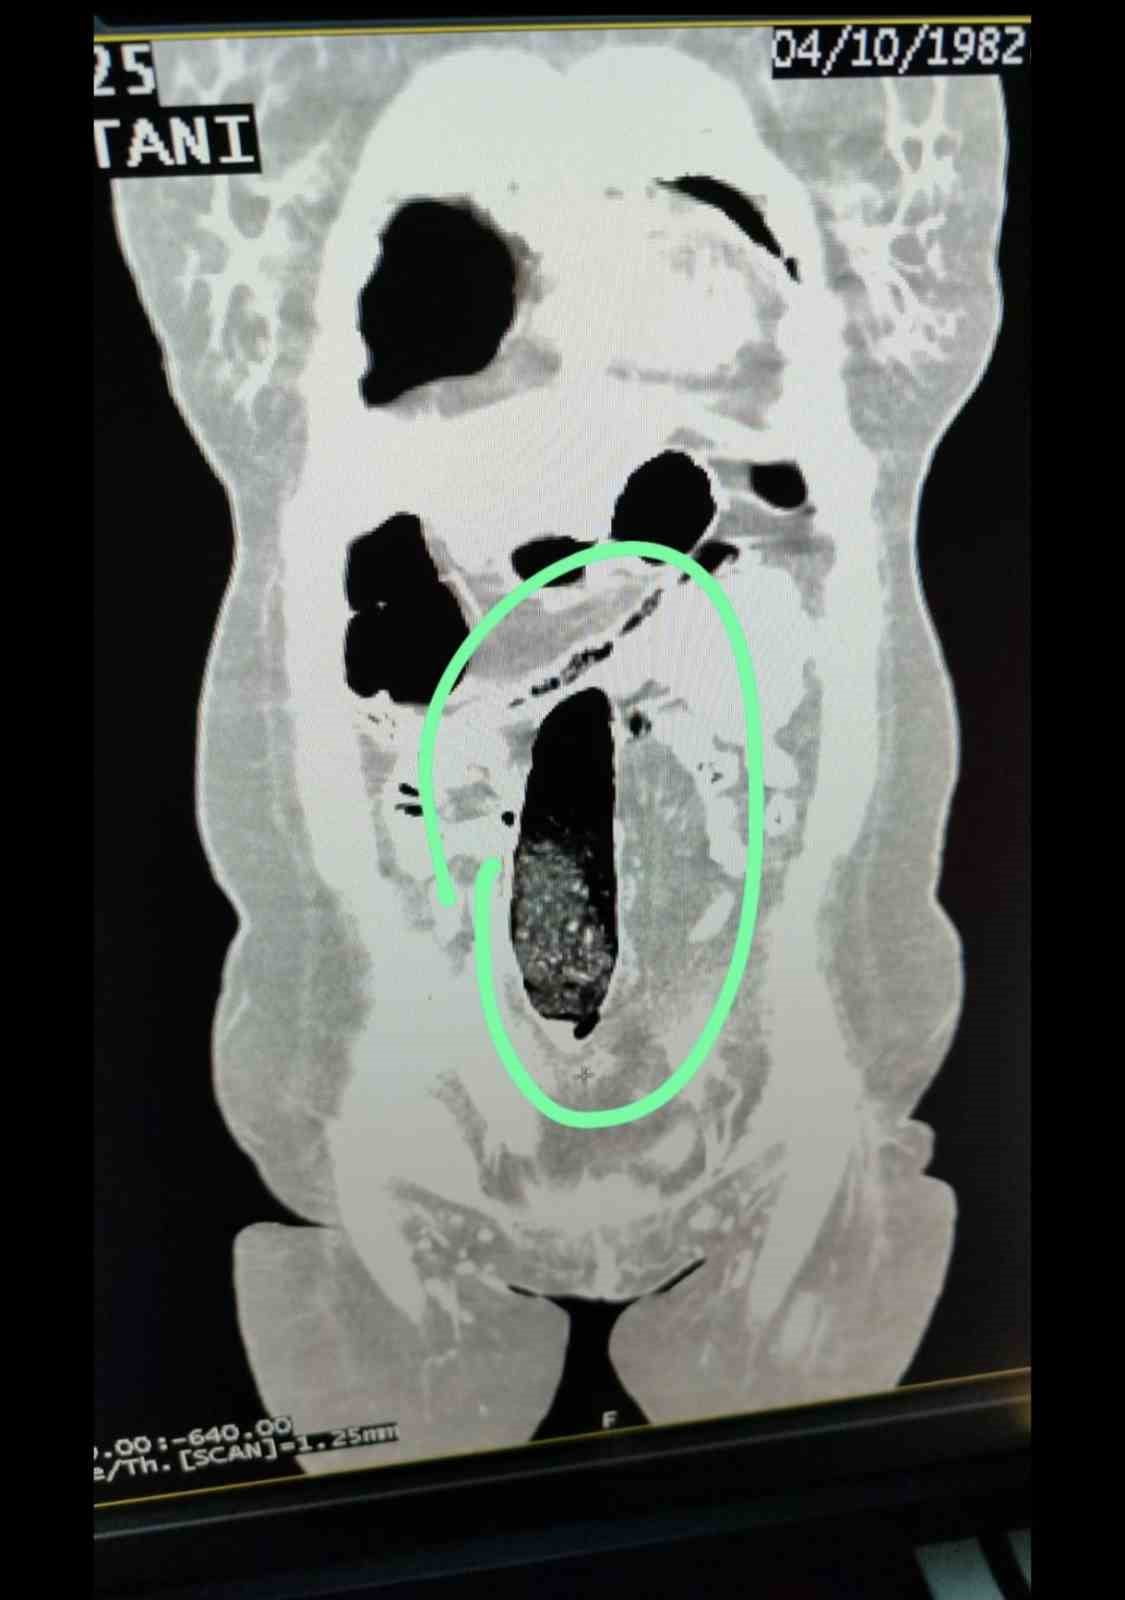

Yapılan kontrollerde şüpheli şahısların iç beden muayeneleri gerçekleştirilmiş; şahısların vücutlarının doğal boşlukları ve bağırsaklarında uyuşturucu madde bulunduğu belirlenmiştir. Tıbbi müdahale ile söz konusu maddelerin çıkarılması sağlanmıştır.

Tıbbi müdahale sonucu, F.V. isimli kadın şahıstan üç parça halinde toplam 397,78 gram metamfetamin ele geçirilmiş; S.İ. isimli erkek şahıstan ise 24 adet sentetik hap ile üç parça halinde toplam 167,68 gram metamfetamin elde edilmiştir.